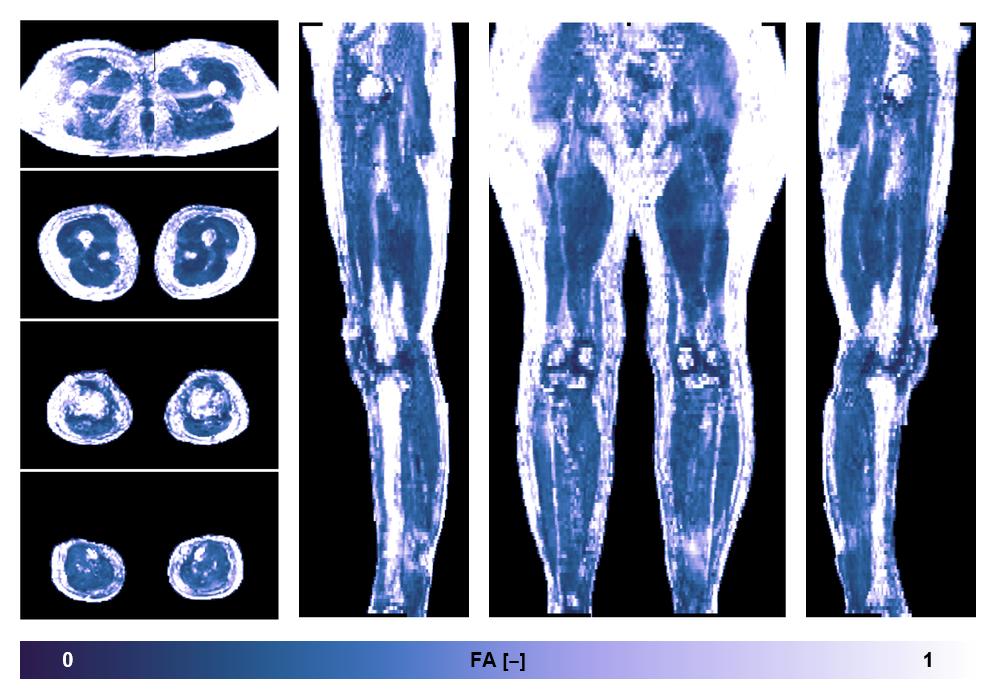

• Fractional anisotropy

IVIM corrected whole leg muscle fractional anisotropy obtained from diffusion tensor imaging.